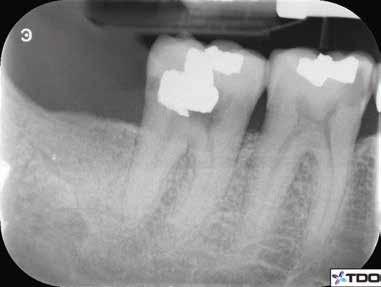

6. a–d. ábrák: A bal alsó második nagyőrlőfogon (3.7) kialakított konzervatív hozzáférési nyíláson keresztül végzett endodonciai kezelés lépései. A mezialis gyökér jelentős mértékben görbült. A gyökértömés hidraulikus kondenzációs technikával készült.

egyszerű obturációs technika, az anyag viszkozitási tulajdonságai és a pulpakamra viszonylag egyszerű tisztíthatósága a kezelésünk prognózisának veszélyeztetése nélkül teszi lehetővé az endodonciai beavatkozások lehető legkonzervatívabb módon történő kivitelezését. A bemutatott esetek ellátása során az Aurum Blue rendszert (Meta Biomed) használtuk a gyökércsatornák megmunkálására, míg a gyökértömés elkészítése során hideg hidraulikus kondenzációs technikát alkalmaztunk a kalcium-szilikát alapú CeraSeal (Meta Biomed) sealer felhasználásával (8. ábra).

Esetbemutatás (2., 3.)

Mindkét esetben irreverzibilis pulpitis miatt vált szükségessé a fogak endodonciai kezelése (6. a-d. és 7. a-b. ábrák). Az esetek ellátása során mindvégig minimálinvazív megközelítést alkalmaztunk. A hozzáférési nyílás kialakításától kezdve az endodonciai kezelés befejezését követő csonkfelépítésig, minden beavatkozás ennek megfelelően történt.